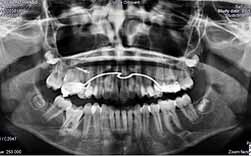

A principal causa de falta de espaço para a erupção de um molar definitivo é a perda precoce de um molar decíduo.

Aquele que provoca maior e mais rápida perda é o segundo molar decíduo superior, seguido do segundo molares decíduo inferior.

Na região molar é rara a existência de obstáculos à erupção como os odontomas.

Quando a perda já se verifica e o exames demonstram a existência de falta de espaço para a erupção dever-se-à recorrer a um dispositivo apropriado para a recuperação do mesmo.